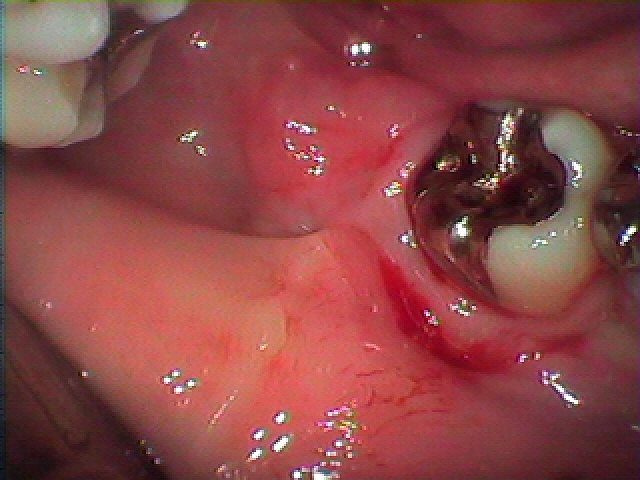

ブログ一覧|広島市安佐南区の歯科医院 ブログ一覧 トップ ブログ一覧 お知らせ スタッフブログ ブログ一覧 お知らせ 2025/02/26 右下の1番部の審美障害にて来院 確かに米粒のような形の被せが入っていました お知らせ 2025/02/26 左上の1番部がグラグラする 近くの歯医者で固定をしてもらったが、、、やっぱり動く きちんと治療したい お知らせ 2025/02/25 右下の奥の親不知の難抜歯 完全に埋まって生えています よく腫れたり匂いがするそうです お知らせ 2025/02/25 左下の奥の親不知の難抜歯 横に生えていますがこのタイプは抜きやすい歯になります お知らせ 2025/02/22 左下の奥の親不知の難抜歯 水平埋伏歯の難抜歯 お知らせ 2025/02/22 右下の親不知水平埋伏歯の難抜歯 ほかの歯医者では抜けないといわれた お知らせ 2025/02/21 交通事故にて前歯が外傷 当時、歯の固定は歯医者にて行っていただいたとのこと 前歯部のインプラント治療 お知らせ 2025/02/21 無歯顎のインプラント埋入をおこなう際にはこのような歯に造影剤入りのレジンにて歯を作りガイド付きのステントを用意して治療計画を建てていきます << 1 2 3 4 5 … 435 436 437 438 439 … 870 871 872 873 874 >> Web診療予約 初めての方へ 選ばれ続ける理由 院内設備について 歯が痛いしみる一般歯科 歯がぐらぐらする歯周病 健康な歯を保ちたい予防歯科 子供の虫歯予防をしたい小児歯科 銀歯をセラミックに審美歯科 白い歯を目指しませんか?ホワイトニング 矯正専門医がいるので安心矯正歯科 抜けた歯を補いたいインプラント・入れ歯 医院案内 スタッフ紹介 メリィハウス歯科クリニックオフィシャルホームページ ラベンダー歯科クリニックオフィシャルホームページ お知らせ・ブログ ホーム 診療科目 一般歯科 歯周病治療 予防治療 小児歯科 審美治療 ホワイトニング 矯正歯科 入れ歯・インプラント マウスピース矯正 初めての方へ 院長・スタッフ 設備紹介 医院案内・アクセス メニューを閉じる